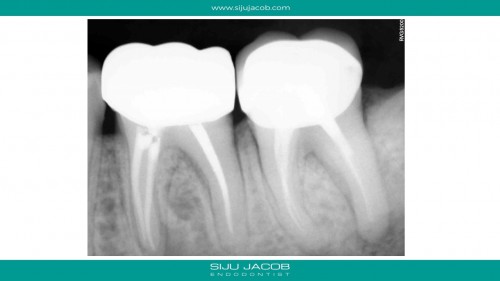

Selective Re-treat of Missed MB2

By Siju Jacob / August 20, 2018